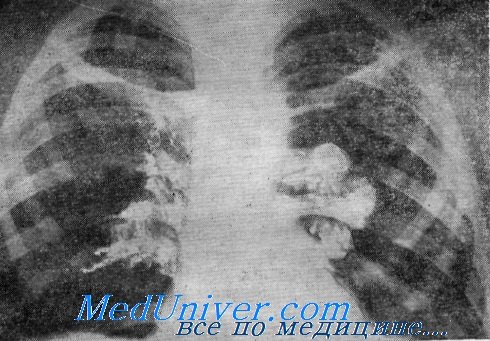

Карнификация Легкого: Микропрепараты и Диагностика

Раздел: Калейдоскоп образов